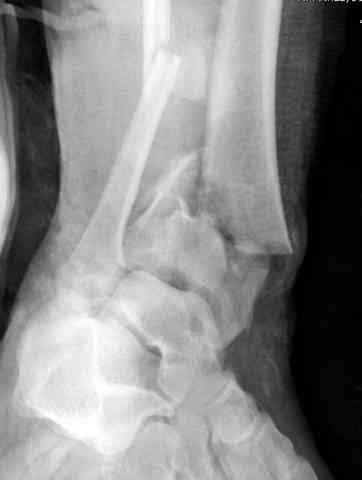

Уважаемые коллеги, оперировать, мне кажется, необходимо. Восстановление суставов, в том числе и столь тяжёлых - не только суть нашей специальности, но и шанс для пациента. В данном случае - молодой женщины. Здесь не нужно ждать результатов КТ - всё понятно и так. Хотите большей ясности - сделайте Ргр без перекрывания металлом плюс добавьте 3/4. Вряд ли стоит откладывать операцию дальше, такие переломы пилона чем раньше оперируешь - тем лучше. Мне кажется, что вряд ли стоит менять классическую пошаговую этапность вмешательства. Дистрактор здесь вряд ли понадобится, кстати. 1й этап - из доступа по заднему краю н\лодыжки отрепонируйте её и фиксируйте 1/3 трубчатой пластиной. Рану не зашивайте. 2й этап. Дальше передним доступом открывайте г\ст сустав, разбирайте *мозаику суставной поверхности*, выстраивайте сустав от наружного фрагмента по тарану, как по матрице. Этот приём всегда использует Виталий Дрягин из Челябинска, признанный эксперт в хирургии этой зоны. Я у него учился. Здесь и неушитый наружный доступ может понадобиться. Суставную поверхность - её отломки - временно фиксируйте спицами и постоянно - винтами. Вот сейчас и, скорее всего, понадобится пластика. И это будет третий этап. И 4й - фиксируйте пластиной - качество кости хорошее, можно и не блокированным *листом клевера*. Есть возможность - блокированной пластиной. Сейчас полно вариантов для пилона. Под ЭОПом контролируйте каждый этап. Раны ушить не забудьте. А главное - не тяните, время уже практически ушло!. И ещё раз - КТ здесь не поможет, а запутать может. Не ждите результатов КТ, сделайте нормальные рентгенограммы и оперируйте. Спасибо. С уважением, Волна

Снова приветствую вас, коллеги. К моменту вступления в обсуждение аксакалов, операция была, увы, выполнена(31.10.07.) Начали с доступа к наружной лодыжке, произвели ее фиксацию спицами, развернули кусок заднего края, наложили дистрактор, затем произвели дистракцию, фиксацию спицами дистального эпиметафиза б/бк,Рентгено-контроль. синтез наружной лодыжки 1/3пластиной. из двух коротких разрезов сформирован канал под медиальную тибиальную пластину LCP. Края ран ушиты без натяжения. Прочувствовать жесткость фиксации винтами с угловой стабильностью не удалось, поэтому дистрактор оставлен на энное время.

На представленных R-снимках не окончательный вид после остеосинтеза. Дистальная опора давила на стопу, пришлось ее сместить проксимально, в рез-те чего, она закрыла щель сустава, последние снимки не информативны.